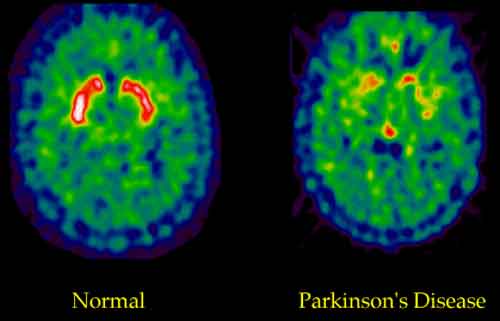

Parkinson: antiossidante a base di sansa, per alleviare sintomi, studiato da ricercatori spagnoli